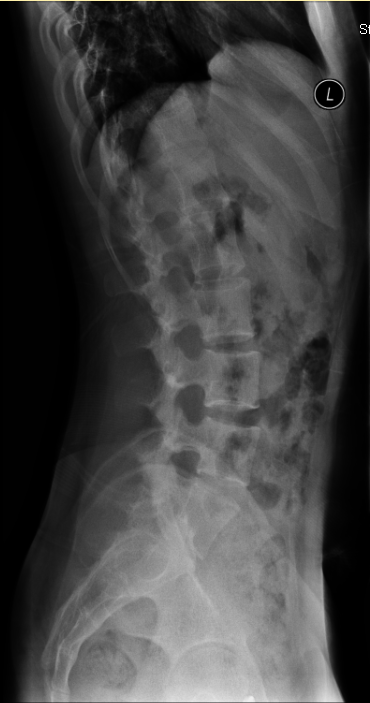

主诉:双下肢乏力4年,加重半年。 病史:患者于4年前无明显诱因出现双下肢乏力,双手支撑地面才能下蹲,无行走困难,无腰部酸痛,无双下肢疼痛、麻木感,大小二便未见异常。半年前,患者诉双下肢乏力及蹲下困难加重,难以下蹲及上下楼梯,无双下肢疼痛、麻木感,大小二便未见异常。遂至外院行MR检查提示:T11-L3水平椎管内蛛网膜囊肿,并相应脊髓圆锥、马尾神经受压移位、聚集。患者一般情况尚可。

诊断:胸腰椎管内占位待查 治疗:入院后尽快完善相关检查,初步明确胸腰椎管内占位原因,初步评估患者病情及是否可进行手术。经治疗组讨论后,拟后路蛛网膜囊肿切除+栓系松解+钉棒内固定术”,术后根据病理决定是否进行下一步治疗。